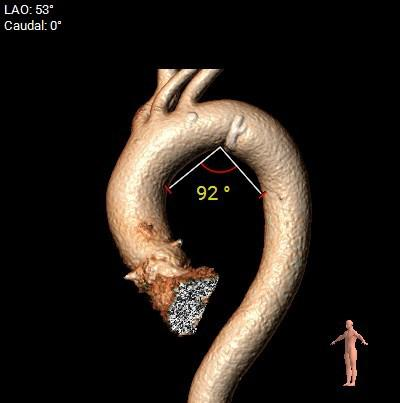

主动脉弓角及弓距可,预估输送器可顺利过弓,必要时Snare辅助:

入路血管走形良好,双侧髂股动脉内径可,入路血管散在附壁钙化,整体入路条件良好:

双侧冠脉高度开口可,窦部较为扁平,左冠瓣叶较长,预估左冠存在一定遮挡风险,球扩及工作位密切关注冠脉血流灌注,必要时冠脉保护。